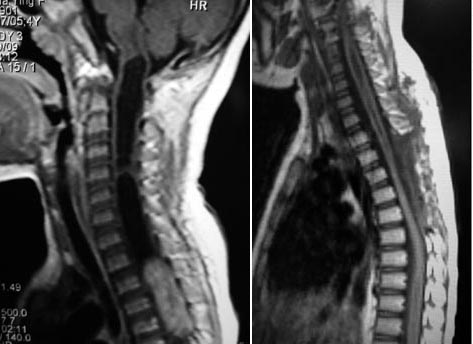

髓内室管膜瘤术前                                                     髓内室管膜瘤术后